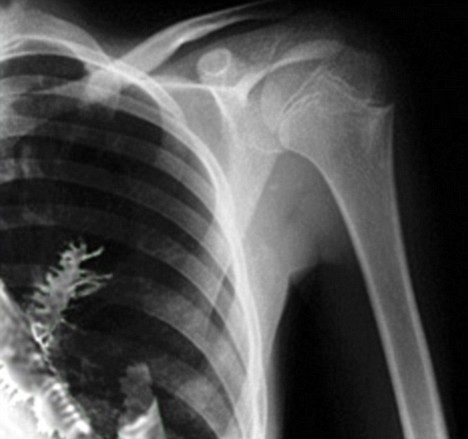

Doctors operating on 28-year-old Artyom Sidorkin was expecting to find a tumor in one of his lungs, but they got a big, green surprise during the surgery:

Doctors x-rayed his chest and found a tumor in one of the lungs. Suspecting cancer, they made a decision to perform biopsy, but when they cut the tissue, they were amazed to see green needles in the cut.

It is obvious that a five-centimeter branch is too large to be inhaled or swallowed, doctors say. They suggest that the patient might have inhaled a small bud, which then started to grow inside his body.